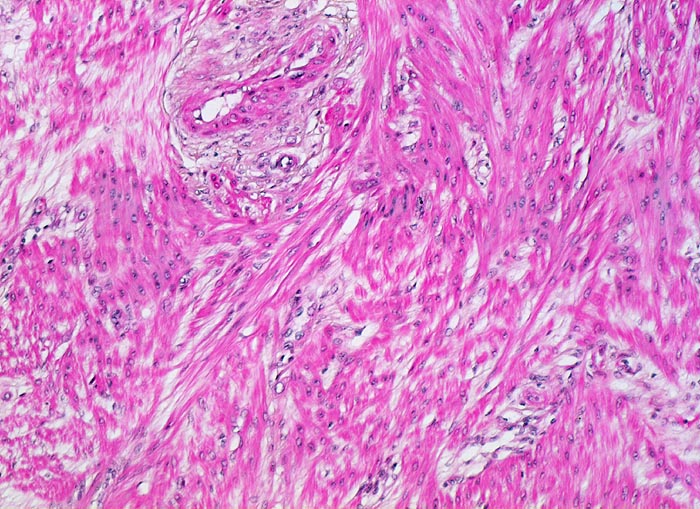

PathoPic ID 5215 - Gravidität: Myometrium

Gravidität: Myometrium

Normalbefund

Plazenta

Hyperplastisches Myometrium mit grossen Myozyten und aufgelockertem Interstitium.

11. Schwangerschaftswoche. Normale Schwangerschaft

Histologie

100